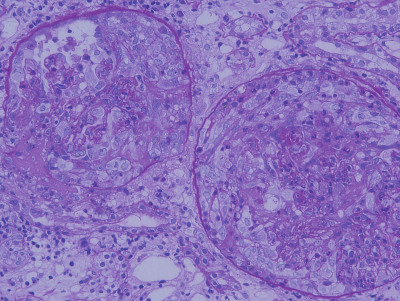

腎生検のPAS染色標本を別に示す。 この病理所見の原因となるのはどれか。

a. 痛風腎

b. 微小変化群

c. ANCA関連血管炎

d. 溶血性尿毒症症候群

e. コレステロール塞栓症